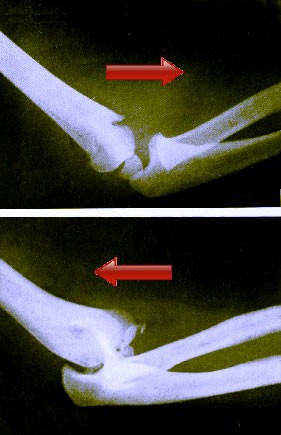

Top - Inward/Forward/Anterior Dislocated Elbow

Bottom: Outward/Backward/Posterior Elbow Dislocation.

Ambroise Paré goes to rather extraordinary lengths to explain what each type of dislocation was, although his explanation creates more confusion than clarity.3 However, Paré talks about inward and outward dislocations of the elbow in a way that suggest they are the same as the forward and backward dislocations of Wiseman, Atkins and Handley. To further confuse things, modern doctors abandoned these descriptions, describing simple elbow dislocations as anterior (aka. forward/outward) and posterior (aka. backward/inward). Of the three names, forward and backward are the most widely used in the period texts and the most descriptive, so that's what will be used in the rest of this section. For those curious what all these things actually refer to, see the image at left for a graphical representation of them.